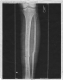

All in all, not a bad set of injuries for someone who just fell six stories. The surgery they had to perform on me is what gave me the wicked robot leg you can see in my profile picture. It's called an external fixator (mono-lateral for you sticklers out there) and it consisted of four 4-5 inch bolts drilled straight into my shin, with a connecting bar on the outside. Because my bones both broke through the skin, casting the leg wasn't an option. They didn't want to put a cast on it and then risk getting the healing flesh infected. Irony would prevail later on, but we'll talk about that when the time comes. I stayed in the hospital for 5 days ( I think) and then went home. I wasn't able to walk without a walker. Crutches were out, because of the healing chest tube wound under my left arm. Oh yeah! The chest tube! I had a tube between my ribs that helped get the fluid out of my lungs. Whenever I coughed, about a teaspoon of mucillagenous orange/yellow fluid would pour from my lung out the tube. It was sick. Moving on! I couldn't use crutches, so I walker'd and wheelchair'd places, but rested mostly.

But back to the leg...my full leg cast stayed on for 34 days, and did it's job well. My leg was immobile, but there was a slight problem. When I went in for x-rays on September 19th, my tibia looked like it hadn't been knitting at all. It was a possibility that because of the infection the healing would be delayed, but stopped altogether? Unlikely. My bone was exhibiting symptoms of nonunion, a permanent break. Bones don't always grow back together. It's not common in properly set and maintained fractures, but it does happen. On the 19th they decided to take my full leg cast off and put me in a patellar tendon cast, which lets me bend my knee but allows no torsion of the lower leg. To stimulate bone knitting, I got an ultrasound emitter that fits into a port on my cast above the fracture.